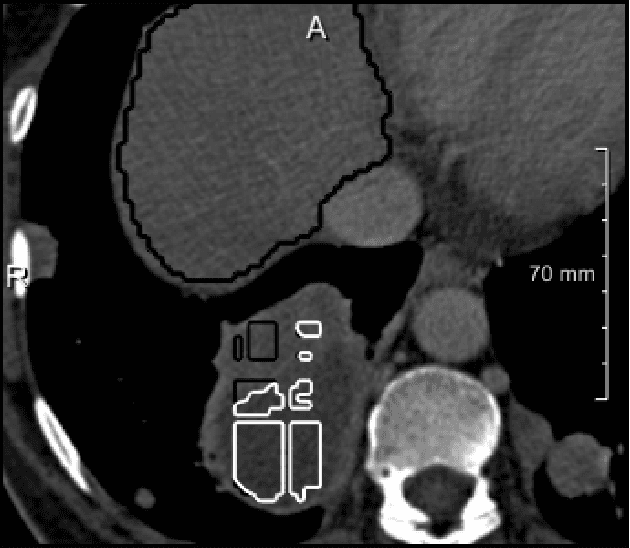

We present a fully automatic method employing convolutional neural networks based on the 2D U-net architecture and random forest classifier to solve the automatic liver lesion segmentation problem of the ISBI 2017 Liver Tumor Segmentation Challenge (LiTS). In order to constrain the ROI in which the tumors could be located, a liver segmentation is performed first. For the organ segmentation, an ensemble of convolutional networks is trained to segment a liver using a set of 179 liver CT datasets from liver surgery planning. Inside of the liver ROI a neural network, trained using 127 challenge training datasets, identifies tumor candidates, which are subsequently filtered with a random forest classifier yielding the final tumor segmentation. The evaluation on the 70 challenge test cases resulted in a mean Dice coefficient of 0.65, ranking our method in the second place.